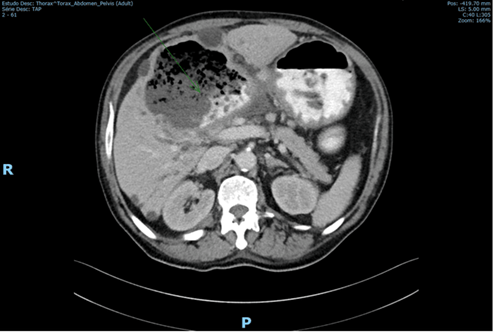

Due to the findings, a C.T. scan was requested (shown in Figure 1 and Figure 2). Several biliary hepatic cysts with varying dimensions were noted, but no hepatic solid lesions were detected. The liver segments IV and V presented with an 11.5 x 9.7 cm non-pure liquid collection, with gastric communication, evidenced by multiple air bubbles and oral contrast. Periceliac and perigastric ganglia were noted. No relevant findings were detected in the thoracic study or the remaining abdomen and pelvis.

Figure 2 Fistula with passage of gastric contents to a hepatic cyst.